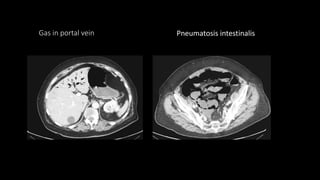

• In severe cases gas may be seen within the bowel wall appearing as

intramural locules of low attenuation.

• Gas may also be seen in the portal venous system as branching

peripheral low attenuation usually in the left lobe of the liver .

Gas in portal vein Pneumatosis intestinalis